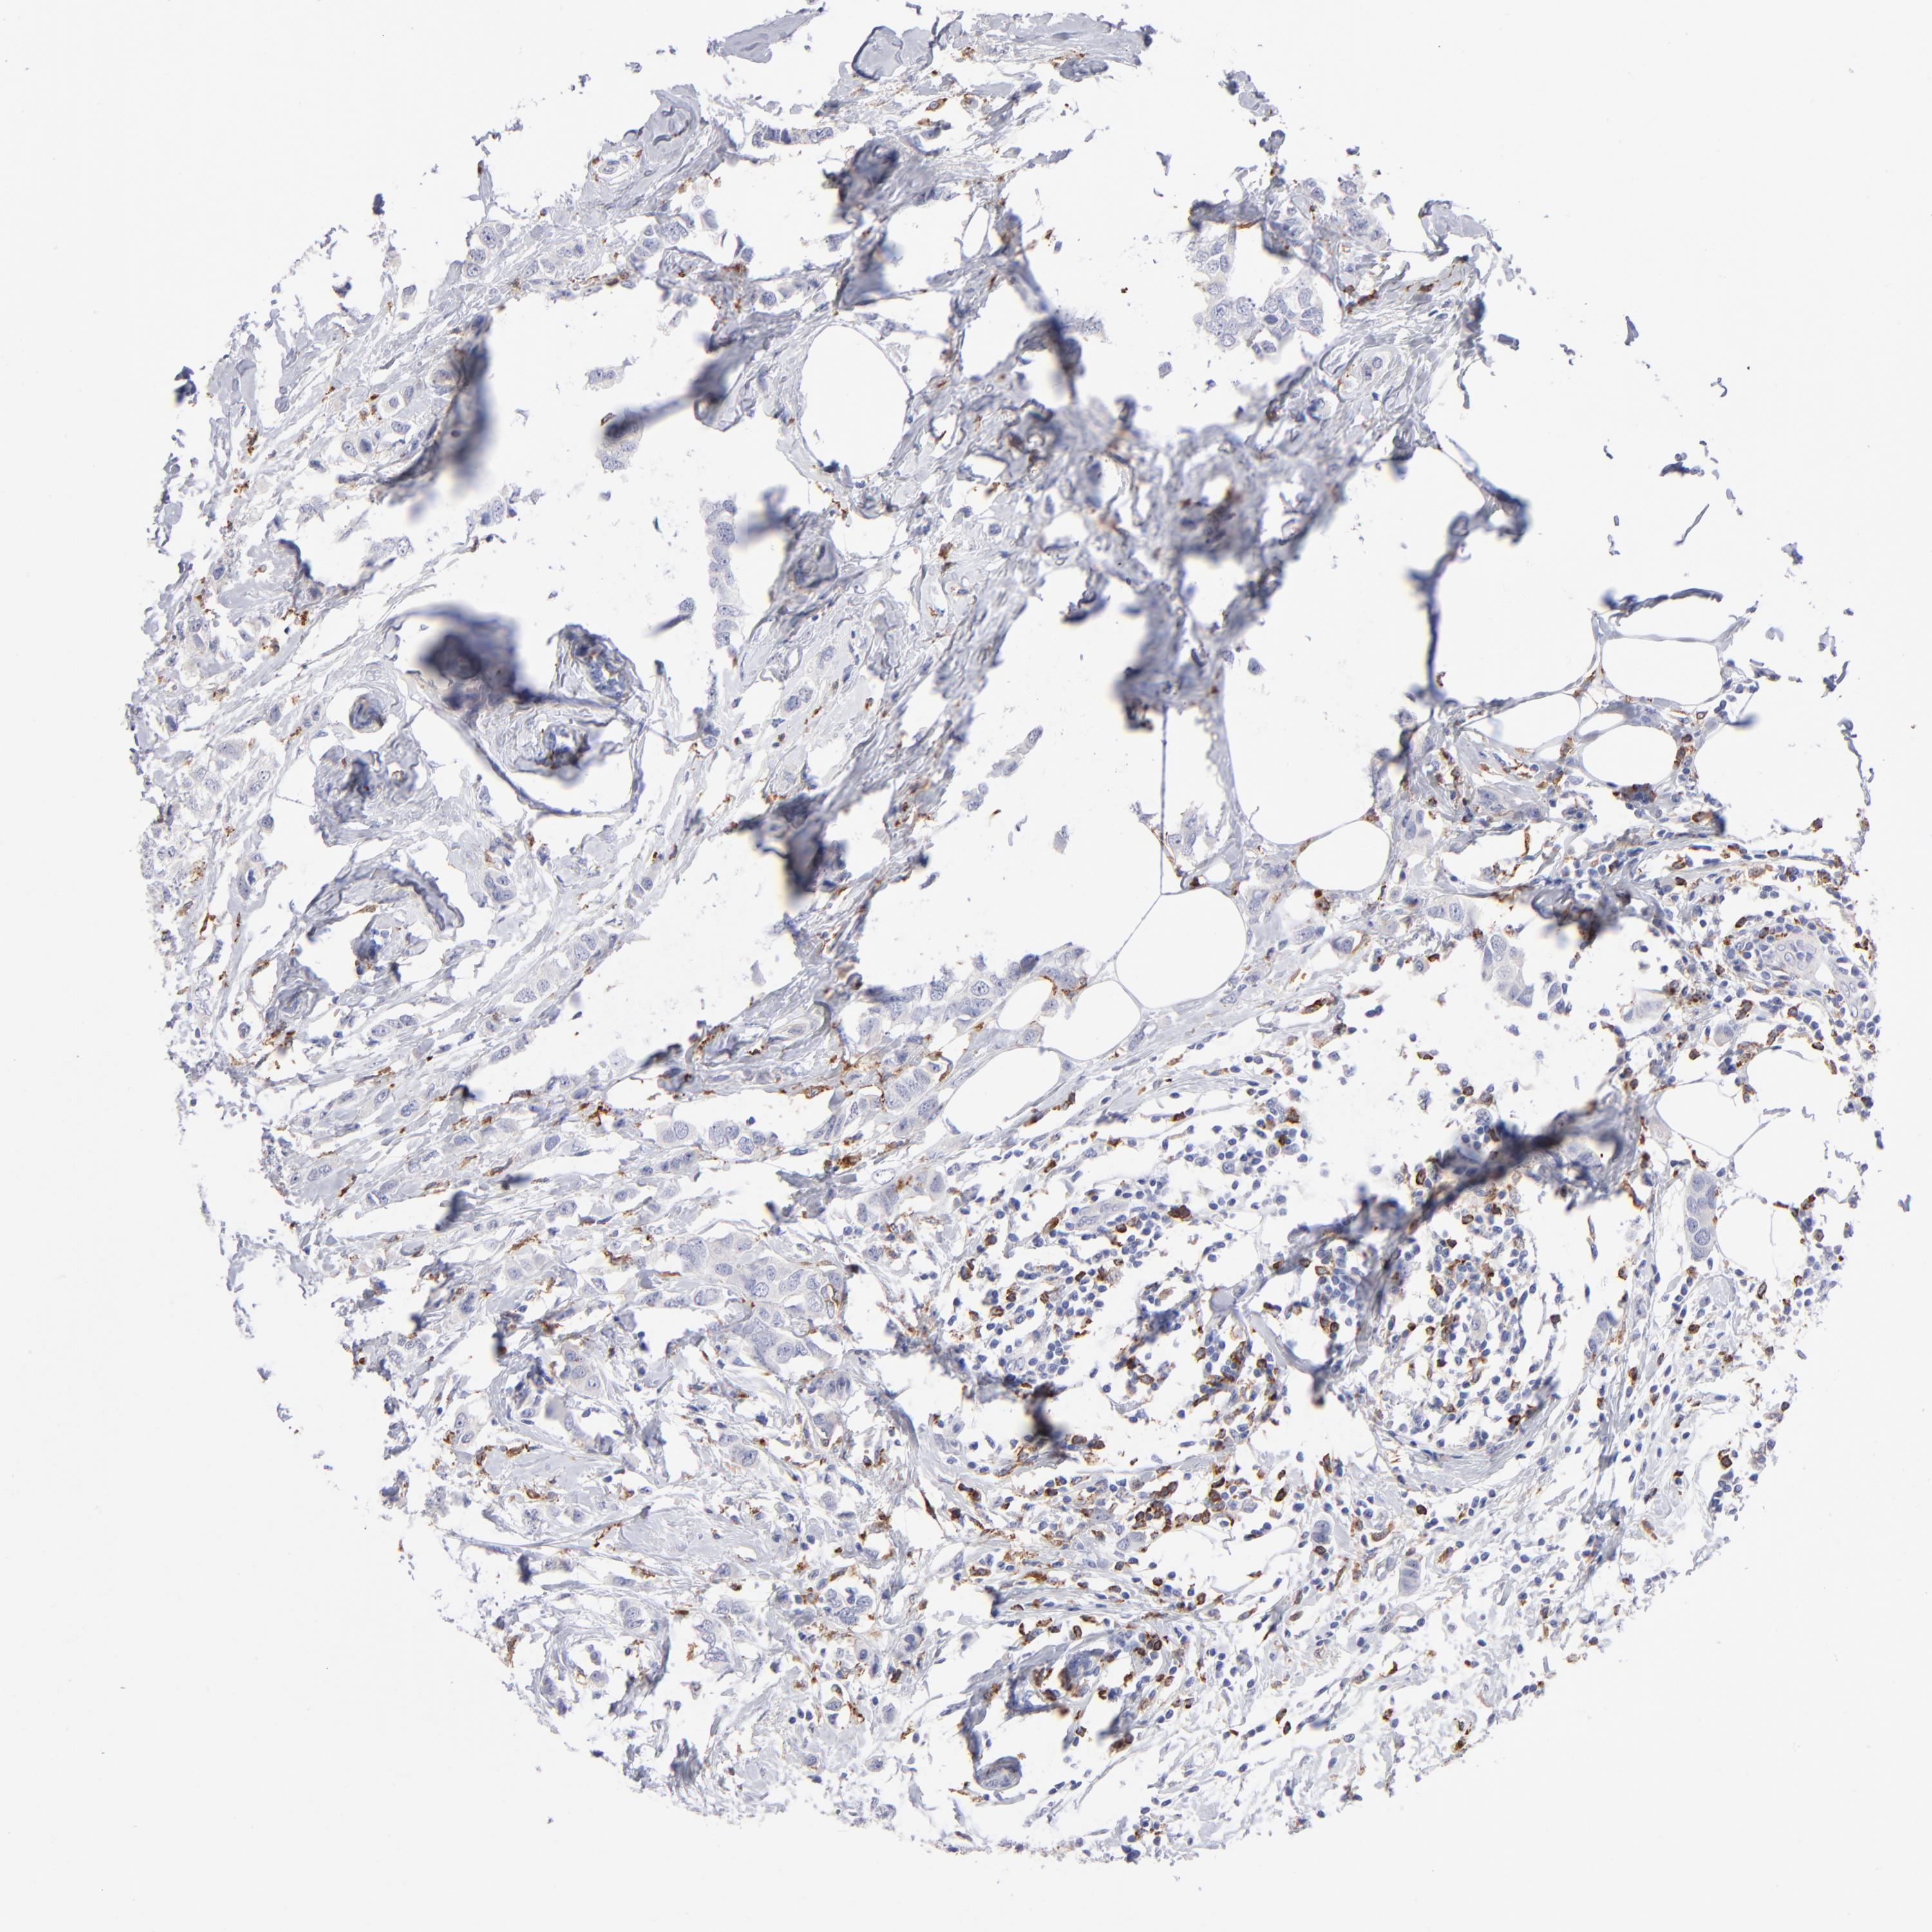

CANCER BREAST CANCER Show tissue menu

BRCA TCGA BRCA VALIDATION PROTEIN EXPRESSION

ANTIBODIES

AND

VALIDATION